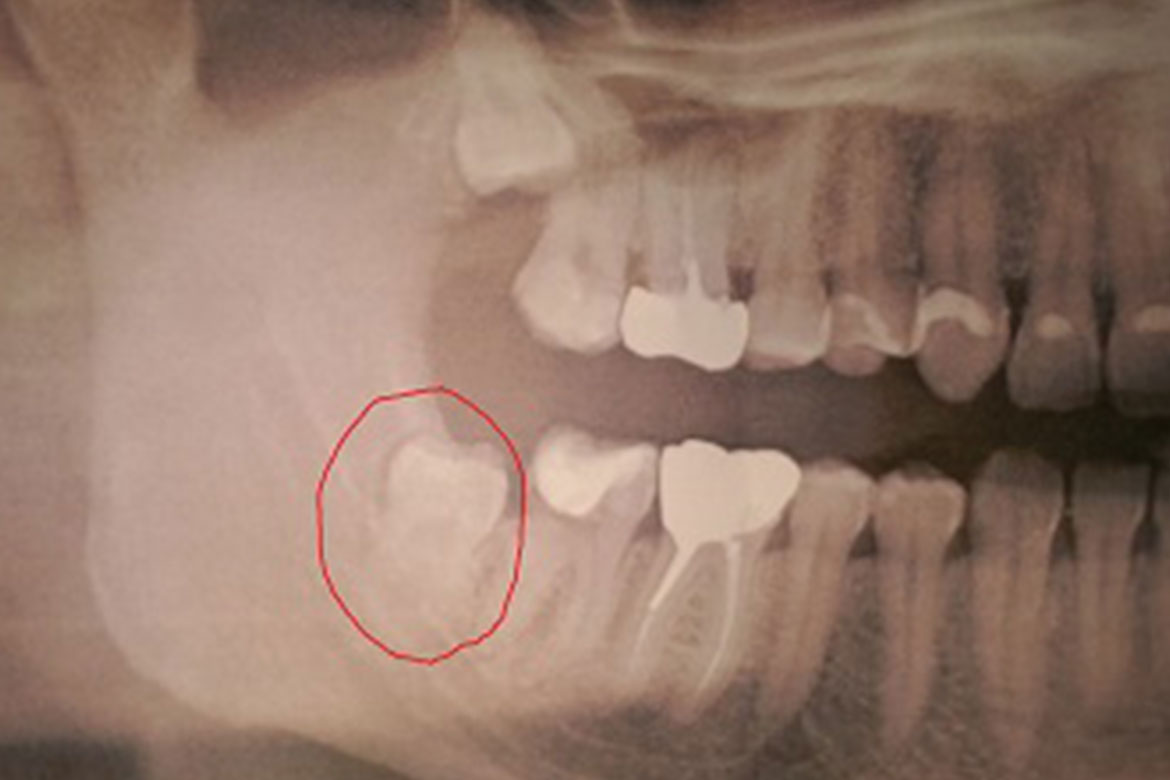

Dents de sagesse